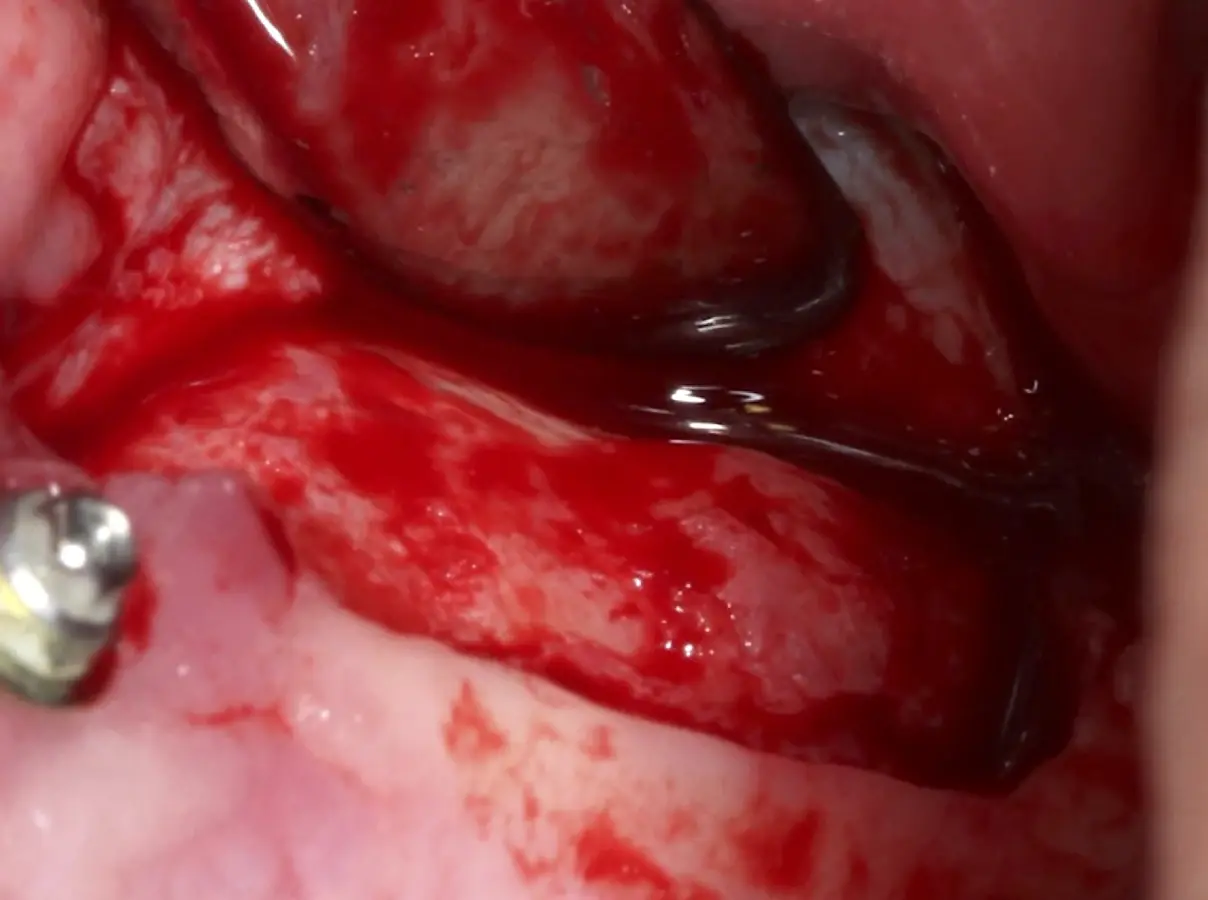

Una vez elevado el piso sinusal según la planificación se realiza la evaluación clínica de la integridad de la membrana y de posibles desgarros a través de la maniobra de Valsalva.24 Consiste en pedir al paciente que respire profundamente y retenga el aire, cerrar la boca, apretar la nariz con los dedos y forzar la salida de aire. Al final de la prueba, es necesario mantener la presión entre 10 a 15 segundos. Se identificará la movilidad de la membrana y la ausencia de burbujas de aire para corroborar que no hay perforaciones. Dependiendo de la decisión clínica se puede optar por adicionar en la superficie de la membrana de Schneider membranas de colágeno o de plasma rico en fibrina (PRF) para dar mayor soporte durante la inserción del biomaterial de relleno óseo (Figura 10).

Figura 10. Membrana de PRF introducida dentro del seno maxilar.

Figura 19. Colocación de membrana de PRF dentro del seno maxilar como protección de la membrana de Schneider.